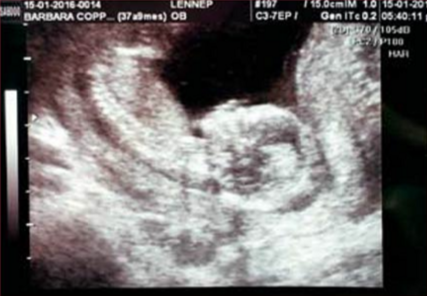

Este ultrasonido se lo realizó el 15 de enero pasado dónde confirmó el sexo del bebé. (Foto: ediciondigital.eluniversalmas.com.mx)

En los comentarios se aprecia que el sexo del bebé que está esperando Bárbara es femenino. (Foto: https://ediciondigital.eluniversalmas.com.mx)